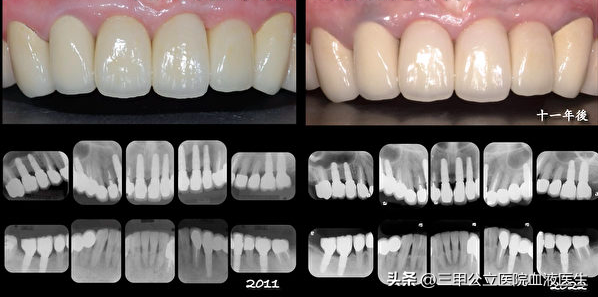

第一:种植牙为什么会失败?种植牙的问世,已经十几年了,在国外已经有非常多的成功案例,然而这种技术,推广到我国,虽然给很多爱美的个体,带来了足够好的美感,但是由于个体已经,技术,甚至材料上的差异,直接造成很多人种植牙失败,

可以说,要种植牙成功,选择信任的,口碑好的口腔医生,以及使用比较好的种植体材料,才是我们种植牙成功的关键。

后续:总之对于选择种植牙,肯定是一种无奈的选择,牙齿当然是自然的最好,日常生活中,一定要好好爱护牙齿,如果真的要种植牙,建议一定要到公立权威性的机构,或者是医院进行判断,治疗,